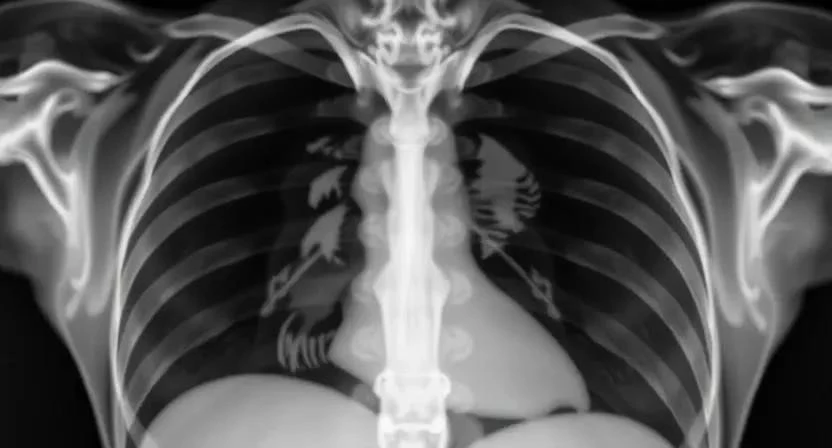

Для точной диагностики причины кашля ветеринар может использовать следующие методы:

- Рентген грудной клетки: Позволяет оценить состояние легких и сердца.